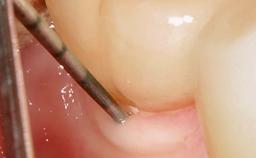

Reconstructive Treatment of a Peri-Implantitis Defect at an Implant in a Mandibular Molar Site

In this case, Mario Roccuzzo utilizes surgical bone regeneration treatment around implant 46 using a bone graft substitute and a connective tissue graft to resolve peri-implant inflammation, reduce the probing depths, and prevent further progression of disease.